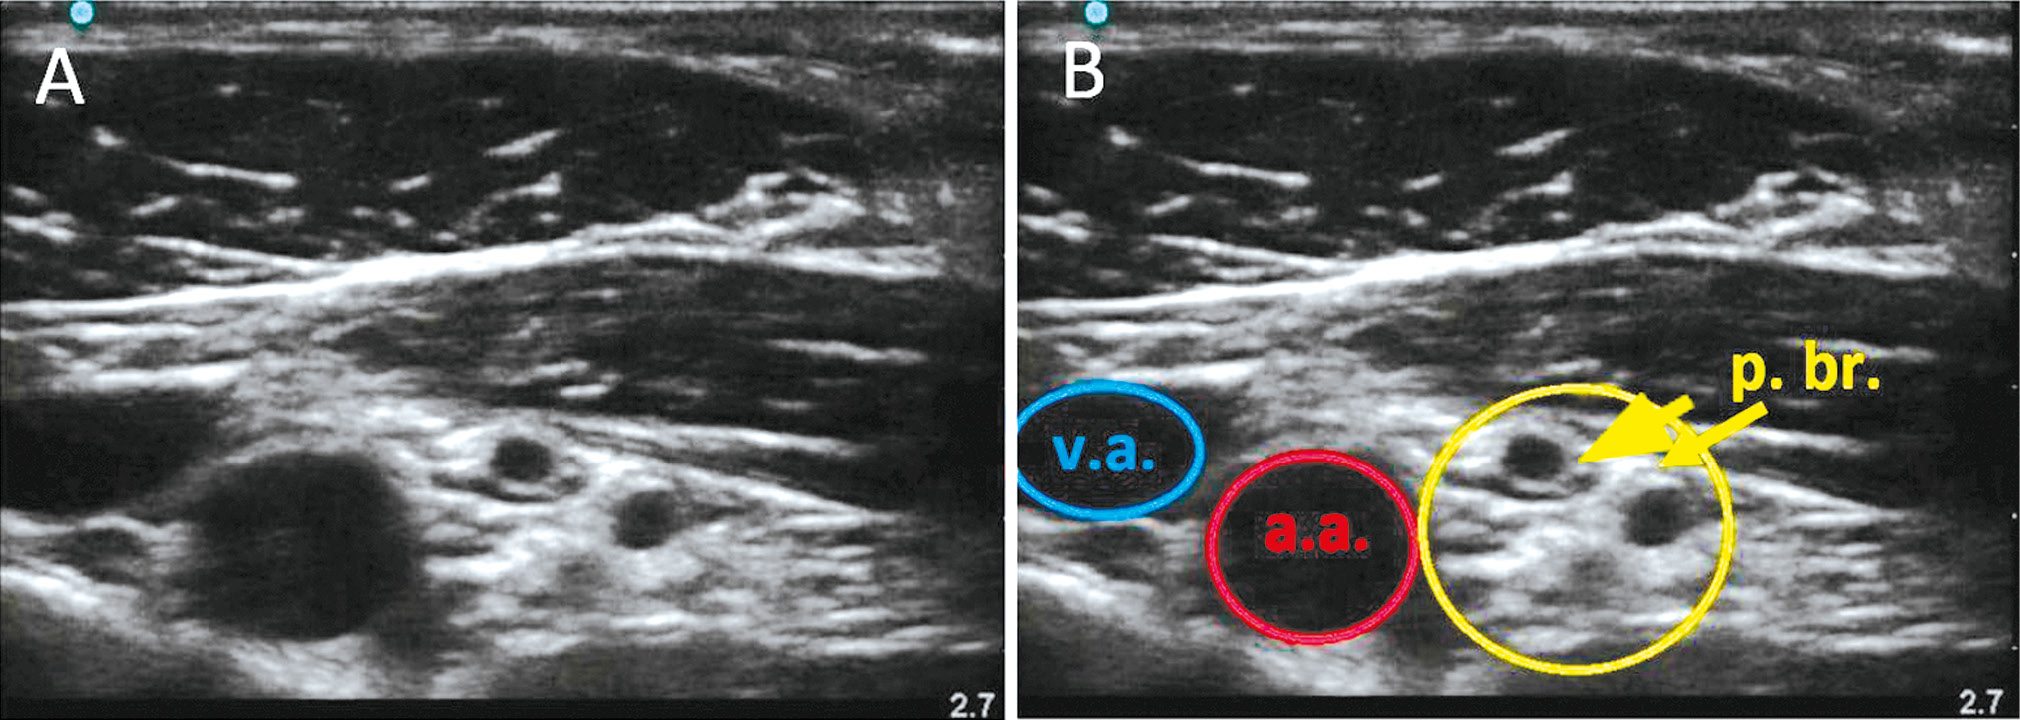

Шаг 3. Сохраняя то же положение датчика, он слегка наклонялся с целью направить ультразвуковой луч краниально, под ключицу. Подбирали оптимальный угол наклона датчика между задней поверхностью ключицы и передней зубчатой мышцей, для того чтобы направить ультразвуковой луч под более прямым углом к нижележащим сосудисто-нервным структурам и тем самым минимизировать анизотропию (рис. 1).

Рис. 1. Сонограмма сосудисто-нервного пучка, полученная по методике модифицированного проксимального подключичного доступа. А – ультразвуковое изображение. В – ультразвуковая картина и схема сосудисто-нервного пучка в подключичной области (v.a. – подмышечная вена, а.а. – подмышечная артерия, p.br. – плечевое сплетение) / Fig. 1. Sonogram of the neurovascular bundle obtained using the modified proximal subclavian approach. A – ultrasound image. B – ultrasound picture and diagram of the neurovascular bundle in the subclavian region (v.a. – axillary vein, a.a. – axillary artery, p.br. – brachial plexus)